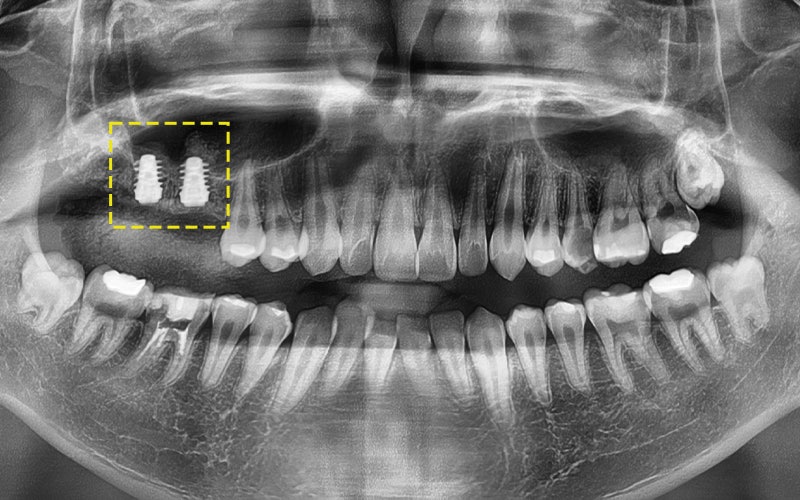

2025.06.18

After carefully considering the oral condition,

we placed the implant in the proper position and direction!

So we recommended and performed surgery using

Swiss Straumann implants, which are recognized

as the longest-lasting and strongest in the world!